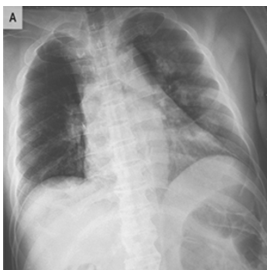

3. Methodology

The study's data set comprised chest X-ray images of both viral and normal pneumonia, as well as those for COVID-19-positive [35, 36]. A total of 21165 chest X-ray images have been included in this dataset which are 3616 COVID-19 positive, 10,192 Normal, 6012 Lung Opacity, and 1345 Viral Pneumonia images. Fuzzy image processing encompasses a collection of techniques designed to interpret, represent, and manipulate images, segments, and functions using fuzzy set theory [13].

First: the performance metrices for the proposed edge detection technique is measured for healthy sample images using MATLAB and Zynq702 FPGA. The results of these performances are shown in Table 2 for 299×299 size images.

Second: the performance metrices for the proposed edge detection technique is measured for infected sample images using MATLAB and Zynq702 FPGA. The results of these performances are shown in Table 3.

Table 2 and Table 3 illustrate both the healthy and infected images, respectivly, the clarity of edges is observed. The tables indicate that using the proposed method with MATLAB led to a significant improvement in edge clarity in the Infected images compared to the healthy ones. This is due to the characteristics of the COVID-19 disease present in the infected images, which increase the complexity of the edges and make them less clear. They also indicate that the images produced by the proposed method are clearer than those from MATLAB, as the proposed method employs fixed-point arithmetic to represent numbers that are closer to edge values than the numbers used by MATLAB, which relies on floating-point arithmetic.

Table 2. Results for normal images

Table 3. Results for COVID-19 infected images